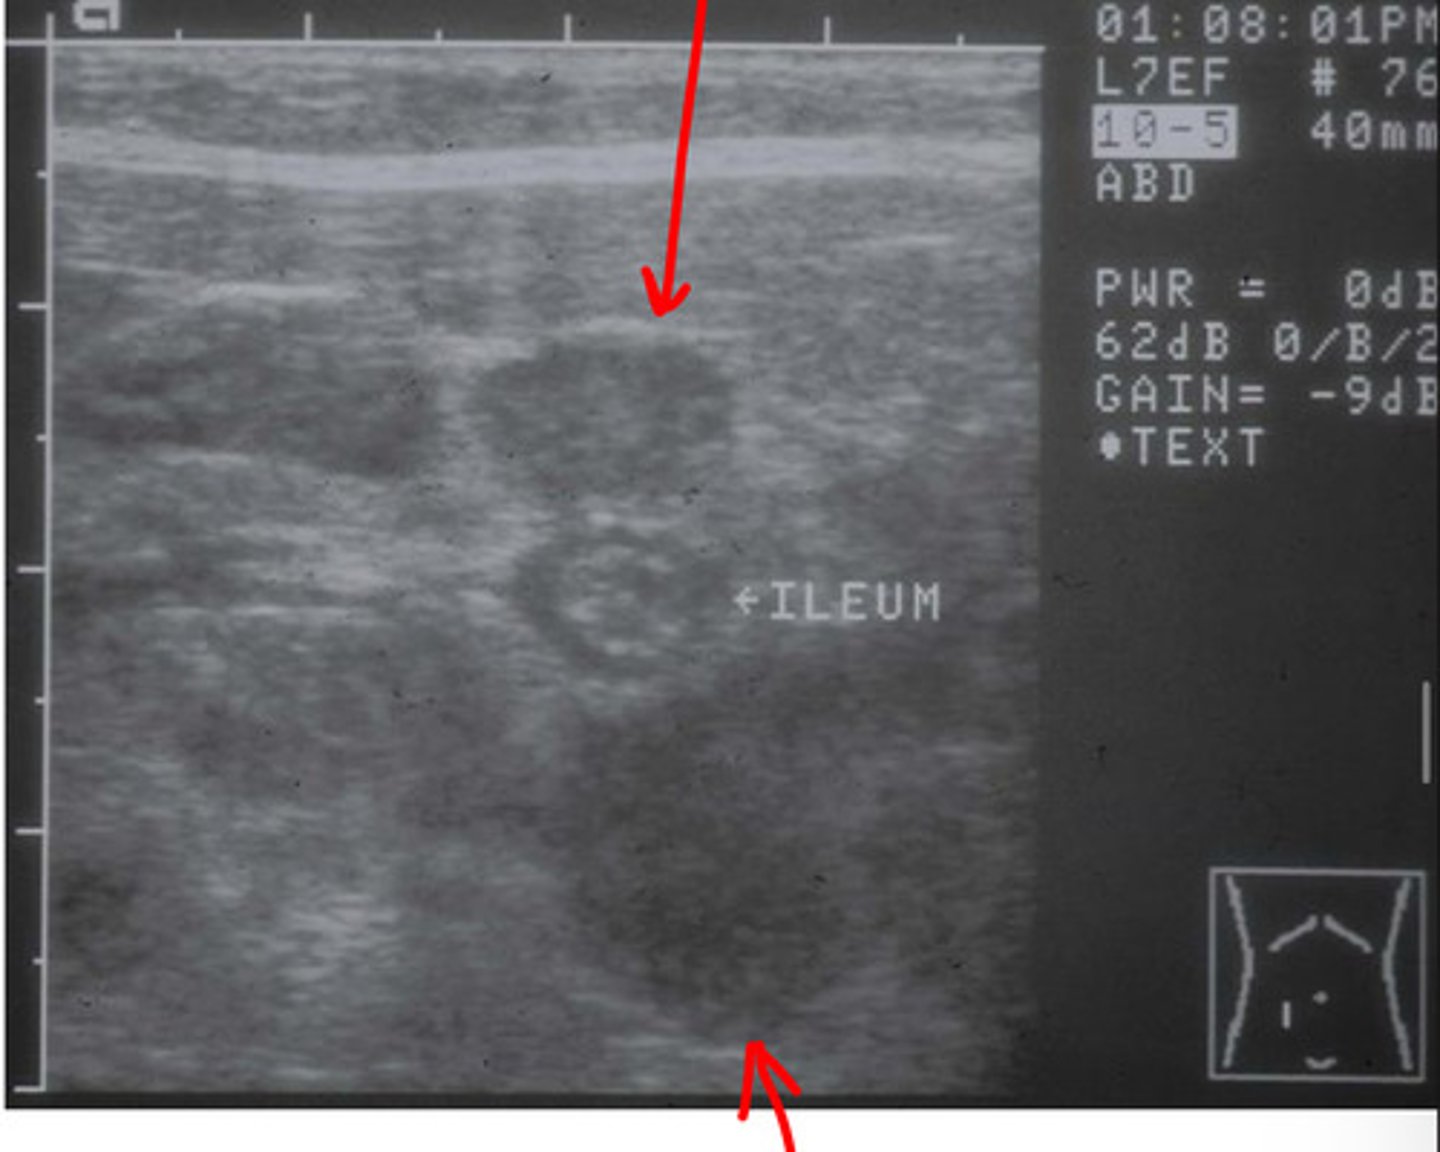

ID structure

lymph node

what structure is this?

lymph node

ID structure

lymph node

ID